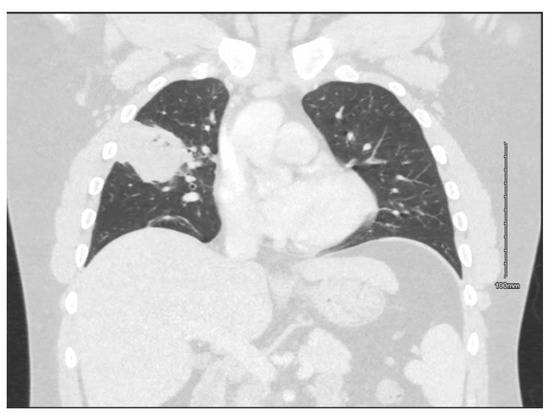

Introduction: Hafnia alvei is a Gram-negative, facultative anaerobic bacillus that is most often found as an enteric commensal. It is seldom considered to be pathogenic in immunocompetent individuals. Case report: We describe a case of a 23-year-old, previously healthy male, who presented to the emergency department with a two-day history of hemoptysis, mild dyspnea, pleuritic chest pain, fevers, and chills. Bloods revealed leukocytosis and elevated C-reactive protein. Chest X-ray and CT of the thorax revealed a cavitating lesion in the right upper lobe. He was commenced on empiric antibiotic treatment with amoxicillin/clavulanate and clarithromycin for community-acquired pneumonia in accordance with local guidelines. He subsequently underwent a bronchoscopy, and the bronchoalveolar lavage sample revealed a heavy growth of H. alvei. Despite the widely documented natural resistance of H. alvei to penicillin, the patient demonstrated complete resolution of his symptoms and initial raised inflammatory markers. Conclusions: We present a case of community-acquired cavitary pneumonia in a previously healthy young adult with H. alvei isolated from bronchoalveolar lavage samples. Parallels are drawn between our case and other cases of H. alvei respiratory isolates in our discussion of its clinical significance. Full article

Show Figures

Figure 1